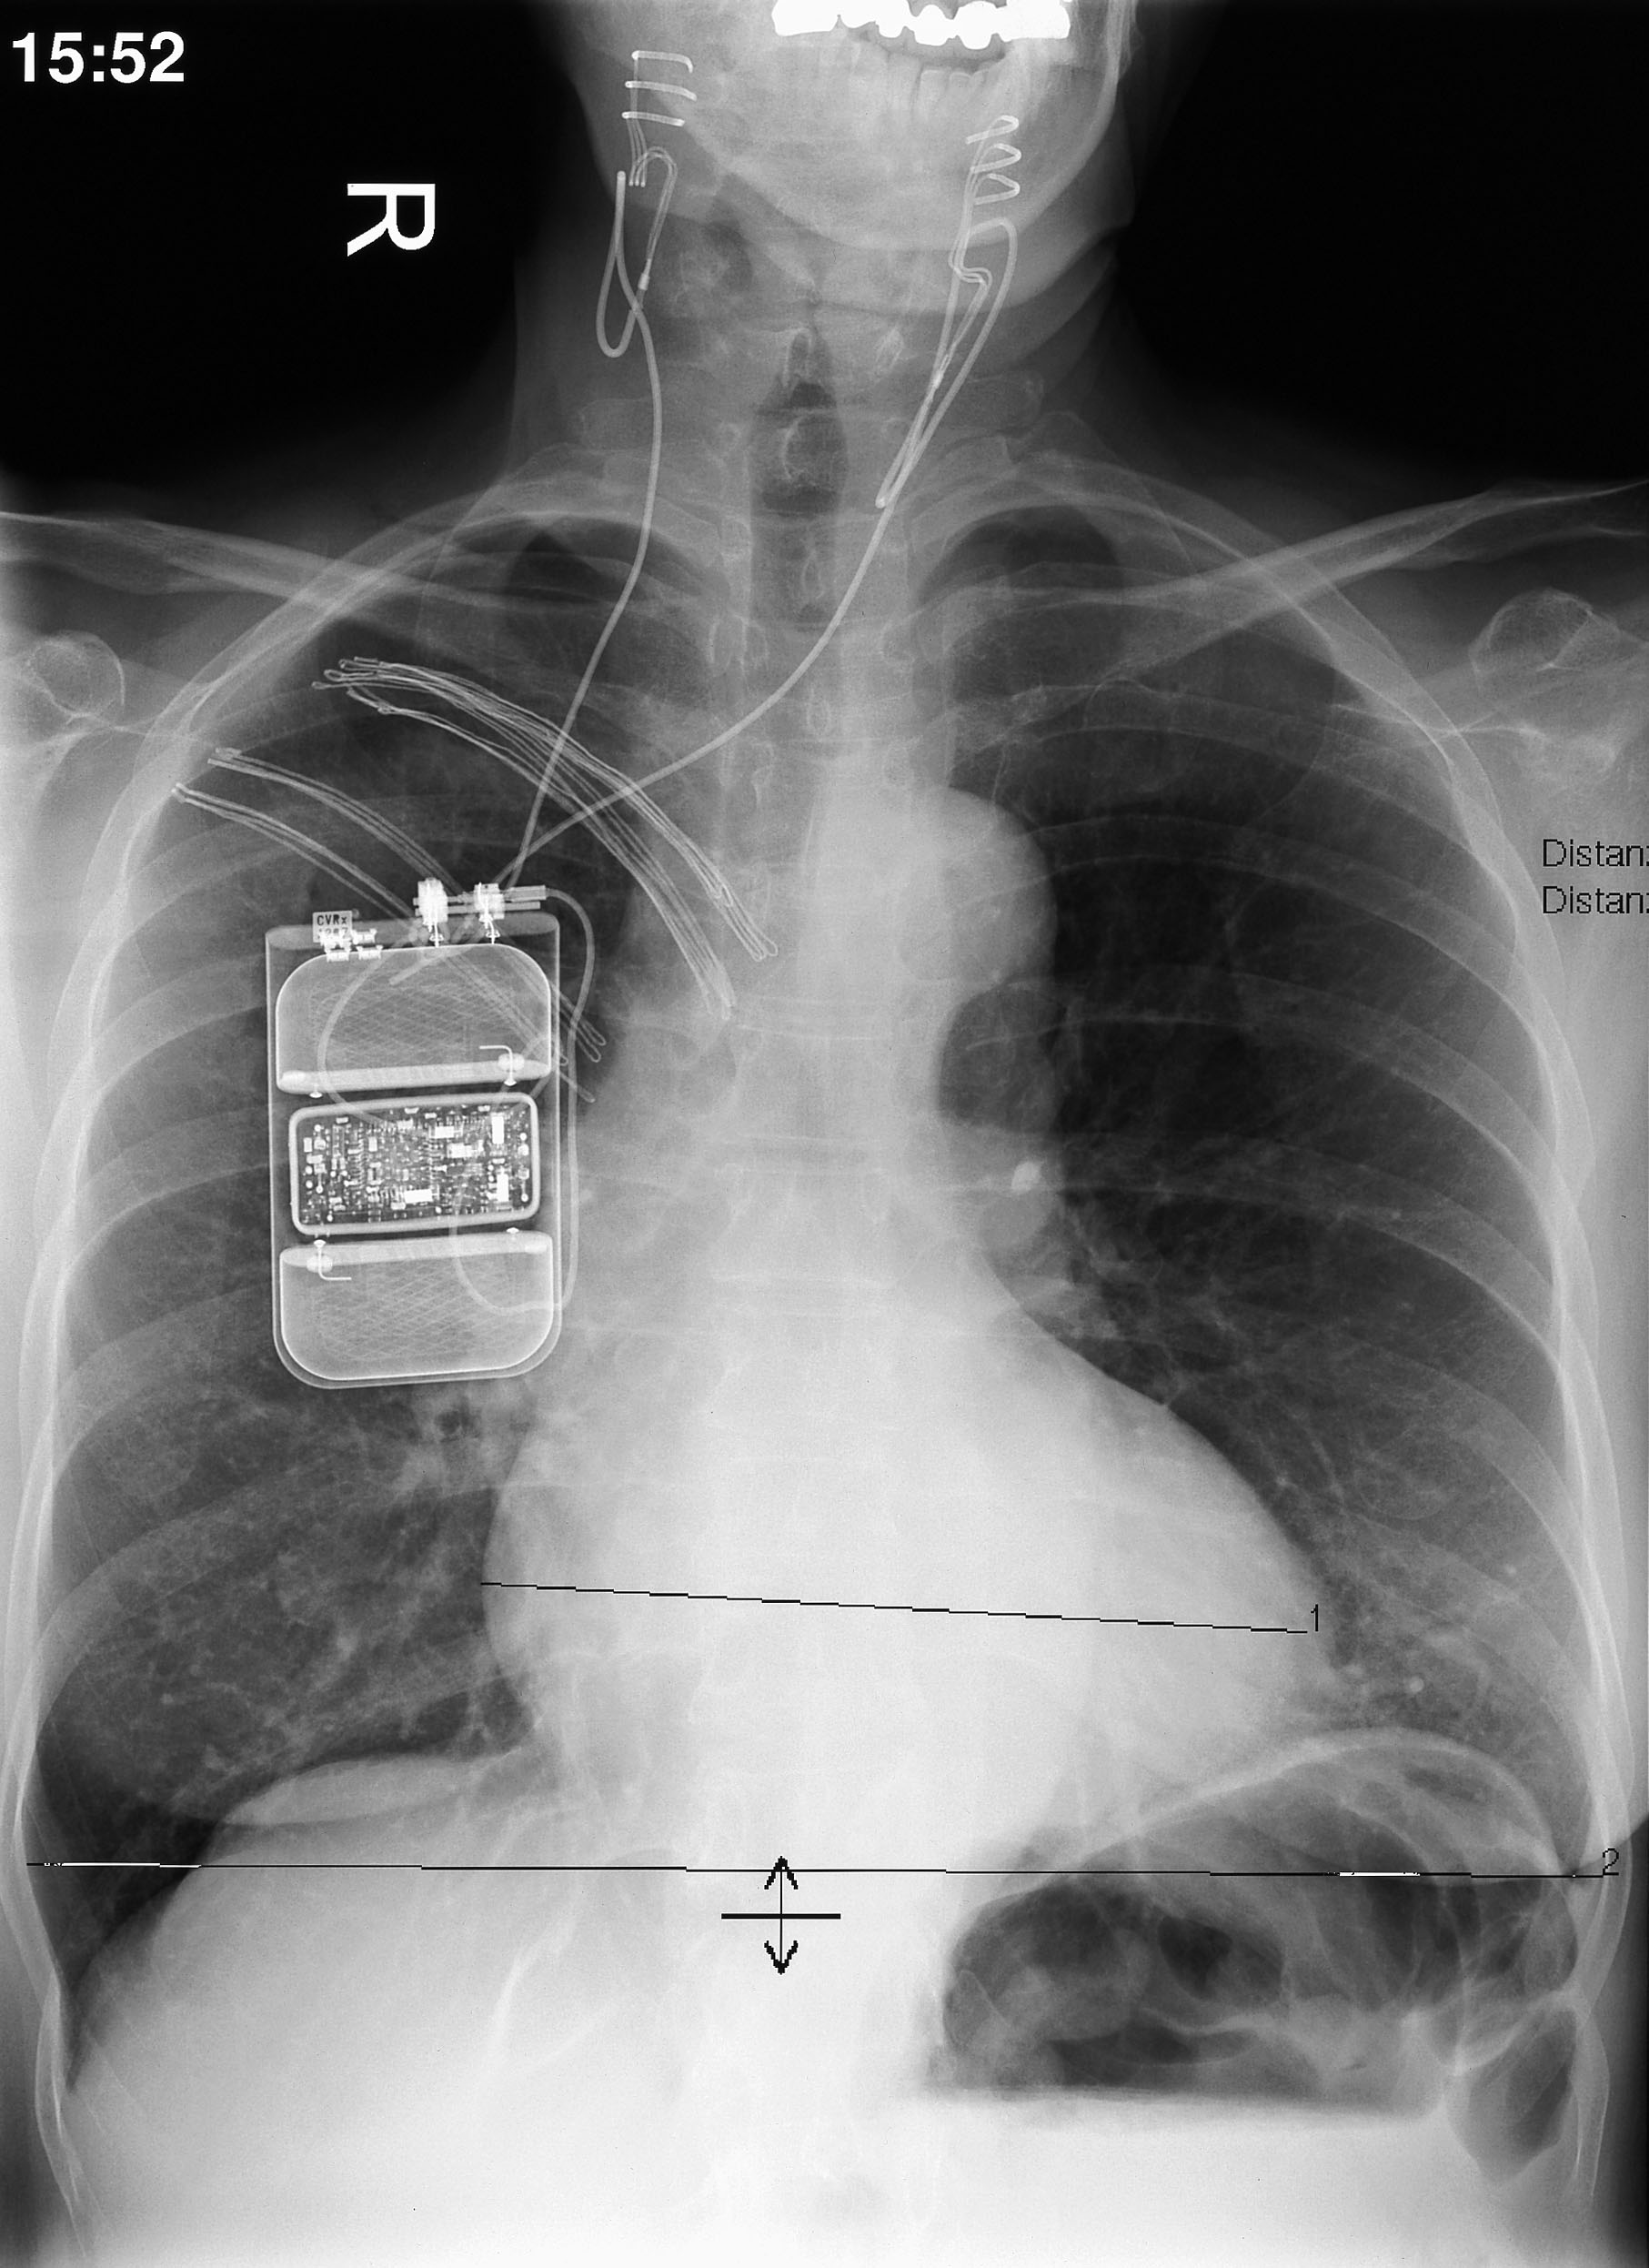

Klein und kompakt wie ein Herzschrittmacher, verspricht ein in Deutschland zugelassenes Gerät Hoffnung für Bluthochdruckpatienten, deren Werte trotz regelmäßiger Medikamentengabe nicht normalisiert werden können. Es stimuliert die Nervenenden an der Halsschlagader und führt damit zu einer dauerhaften Blutdrucksenkung.

Als eine von drei Studienteilnehmern in Bad Oeynhausen nimmt Karola Söfker an der DEBuT-HAT-Studie teil, an der sich vier Herzzentren in Deutschland mit zunächst zwölf Patienten beteiligen. In Vollnarkose werden ihr um beide Halsgefäße Stimulationselektroden gelegt. Sie sind mit einem Schrittmacher verbunden, der unter die Haut implantiert wird. Durch die Stimulation werden den blutdruckregulierenden Zentren im Gehirn noch höhere Werte „vorgespielt“. Eine Absenkung der Blutdruckwerte ist die Folge. Der unkomplizierte Eingriff dauert etwa drei Stunden.

Seit einigen Monaten steht jetzt ein neues, kleineres Gerät zur Verfügung, dass außerhalb von Studien eingesetzt werden kann. Es ist mit nur noch einer Elektrode verbunden, die auf ein Halsgefäß aufgenäht wird. Der Schrittmacher ist kleiner bei längerer Laufzeit der Batterie, so dass ein Wechsel nicht mehr so häufig erforderlich ist. Aktuell bieten nur fünf Zentren in Deutschland die Baroreflexstimulation routinemäßig an. Das Herz- und Diabeteszentrum NRW führt Gespräche mit den Krankenkassen. „Patienten, bei denen trotz komplexer Kombinationstherapie die Hypertonie unkontrolliert ist, haben ein hohes Risiko, innerhalb von zehn Jahren einen Herzinfarkt oder einen Schlaganfall zu erleiden“, erläutert Prof. Dr. Dieter Horstkotte, Direktor der Kardiologischen Klinik. „Die Baroreflexstimulation ist für diese Hochrisikopatienten die richtige Therapie.“

• Weltweit ca. 200 Systeme (Fa. CVRx)